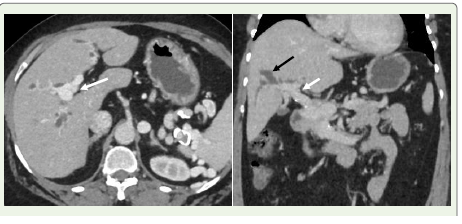

Figure 12:A 55-year-old woman diagnosed with portal hypertension. (A) Axial

contrast-enhanced CT image reveals cavernous transformation of the portal

vein (white arrow). (B) Coronal contrast-enhanced CT scan shows dilated

biliary ducts (black arrow) secondary to external compression from the portal

cavernoma (white arrow), indicative of portal biliopathy.

Portal biliopathy refers to a collection of abnormalities affecting

the bile ducts and gallbladder, typically seen in individuals with

extrahepatic portal vein obstruction or portal hypertension [31].The condition arises primarily through two mechanisms: first, by direct mechanical pressure on the biliary tract from a portal cavernoma [Figure 12] and second, through peribiliary fibrosis triggered by inflammation or ischemia following thrombosis in the

small venous channels within the bile duct wall [4,9,32]. A portal

cavernoma is a network of dilated collateral veins surrounding the

common bile duct, resulting from cavernous transformation. It is

composed of paracholedochal veins (also known as the plexus of

Petren) and epicholedochal veins (plexus of Saint), both of which run

along the bile duct wall [33].

or jaundice [4,9,31].Imaging findings:

Contrast-enhanced CT is typically performed to rule out

alternative causes of biliary dilation, especially since portal biliopathy

can resemble malignant distal bile duct strictures, such as those from

pancreatic cancer or cholangiocarcinoma [34]. The most characteristic

radiologic sign, apart from detecting a portal cavernoma, is the

abrupt bending or “kinking” of the common bile duct, usually due to

external pressure from enlarged paracholedochal veins [35].Management: